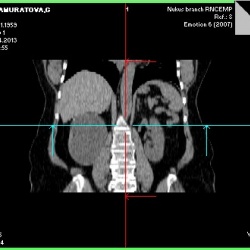

Пациента несколько месяцев беспокоят боли в пояснице, периодические, к медикам ранее не обращался. К сожалению на консультацию был предоставлен единственный снимок,который произведен по назначению...

Больного клиники нет. Выявился случайно.

Здравствуйте уважаемые коллеги.Собственно дама 40 с хвостиком.С предв. диагнозом правосторонняя почечная колика.Смущает ЧЛС справа,но еще больше расширенный мочеточник с той же стороны.Интересно ваше...